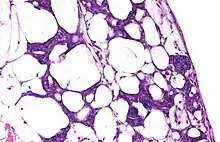

During the last century, blastemas were thought to be composed of undifferentiated pluripotent cells, but recent research indicates that in some organisms blastemas may retain memory of tissue origin.[3] They are typically found in the early stages of an organism's development such as in embryos, and in the regeneration of tissues, organs and bone.[4]

Some amphibians and certain species of fish and two species of African spiny mice can produce blastemas as adults.[5] For example, salamanders can regenerate many organs after their amputation, including their limbs, tail, retina and intestine.[6] Most animals, however, cannot produce blastemas.

When the limb of the salamander is cut off, a layer of epidermis covers the surface of the amputation site. In the first few days after the injury, this wounded epidermis transforms into a layer of signaling cells called the Apical Epithelial Cap (AEC), which has a vital role in regeneration. In the meantime, fibroblasts from the connective tissue migrate across the amputation surface to meet at the center of the wound. These fibroblasts multiply to form a blastema, the progenitor for a new limb.[7]

As stated above, there are several different types of organisms that can utilize a regenerative blastema as an adult. These organisms include urodele amphibians, zebrafish, and planarian flatworms as major creatures of study. In flatworms, the formation of a blastema needs adult stem cells that are called neoblasts for any type of regeneration to occur.[11] Flatworms use these undifferentiated cells for regeneration after paracrine factors can provide signals from the surface of the wound. The cells in the blastema are also referred to as clonogenic neoblasts (cNeoblasts) that are able to move to the site of the wound and reform the tissue.[12] In urodele amphibians, studies suggest that dedifferentiation of cells leads to the formation of a blastema that is able to form multiple tissue types after the amputation of their tails and wound healing occurs.[13][14] In zebrafish, and in general, it seems as if experts are still uncertain of what truly forms the blastema. However, two common theories that have often been expressed are cell dedifferentiation and the recruitment of stem cells to the wound site.[15]